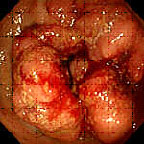

Ο καρκίνος του παχέος εντέρου είναι ο καρκίνος που αναπτύσσεται στο παχύ έντερο και ορθό (Εικόνα 1). Υπάρχουν και άλλοι -σπανιότεροι- τύποι καρκίνου που αναπτύσσονται στο παχύ έντερο.

Εικόνα 1. Ενδοσκοπική εικόνα καρκίνου του παχέος εντέρου